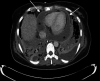

A 44-year-old previously well woman presented with features of respiratory sepsis including a productive cough and fevers, with a recent preceding influenza-like illness. She was diagnosed with community-acquired pneumonia on chest radiograph, influenza infection via nasopharyngeal swab and Streptococcus pneumoniae bloodstream infection with associated purulent pericarditis. She was managed with pericardial drainage and concurrent treatment with antibiotics and made an excellent recovery. This case highlights the complications of both influenza and S. pneumoniae infections, and the importance of prevention via vaccination.